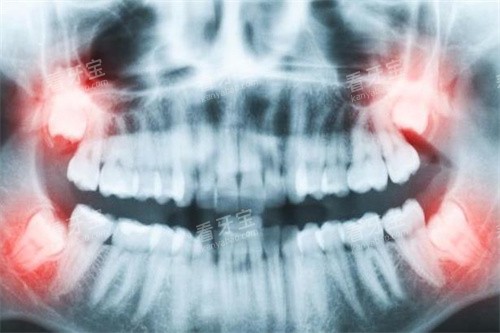

在苏州古城区人民路上,有一家已经服务市民三十余年的口腔专科医院——苏州华夏口腔医院。作为二 级专科医院,这里从1992年成立至今,已经发展成为拥有120张独立诊疗椅、三个院区的大型口腔医疗机构。每天清晨,总能看到不少市民早早地来排队挂号,其中不乏祖孙三代都在这里看牙的忠实患者。

"医生,我想询问下种植牙的价格。"在种植科门诊,这是更常听到的问题。确实,随着技术的普及,种植牙已经成为缺牙修复的主流选择。在华夏口腔医院,种植牙的价格区间相对宽泛,从3980元到20000元不等,这主要取决于患者选择的种植体品牌和自身口腔条件。

韩系种植体是性价比之选,价格在6000元起步,比如奥齿泰TS3型号价格为7599元/颗。这类种植体适合预算有限但又希望获得较好质量的患者。美国皓圣种植体定位中高端,价格从7500元起,其特点是手术创伤小、改善快。对于追求长期稳定性的患者,瑞士ITI种植体是不错的选择,价格14500元起,而瑞典诺贝尔种植体作为高端品牌,价格则从16500元起。

值得注意的是,种植牙费用不仅包含种植体本身,还包括手术费、麻醉费、修复体费用等。医院会为每位患者制定个性化方案,比如骨量不足的患者可能需要可靠行骨增量手术,这部分费用另计。另外,半口或全口种植的价格在6万至30万元之间,具体取决于种植数量和修复方式。